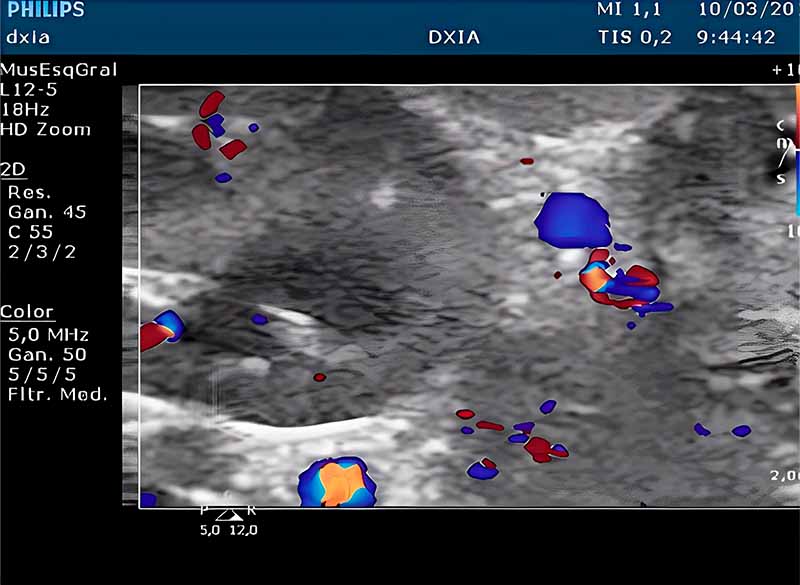

Estudio Eco-Doppler Abdominal:

Realizado bajo sedación. Se localizó comunicación vascular extrahepática de localización craneal al riñón.